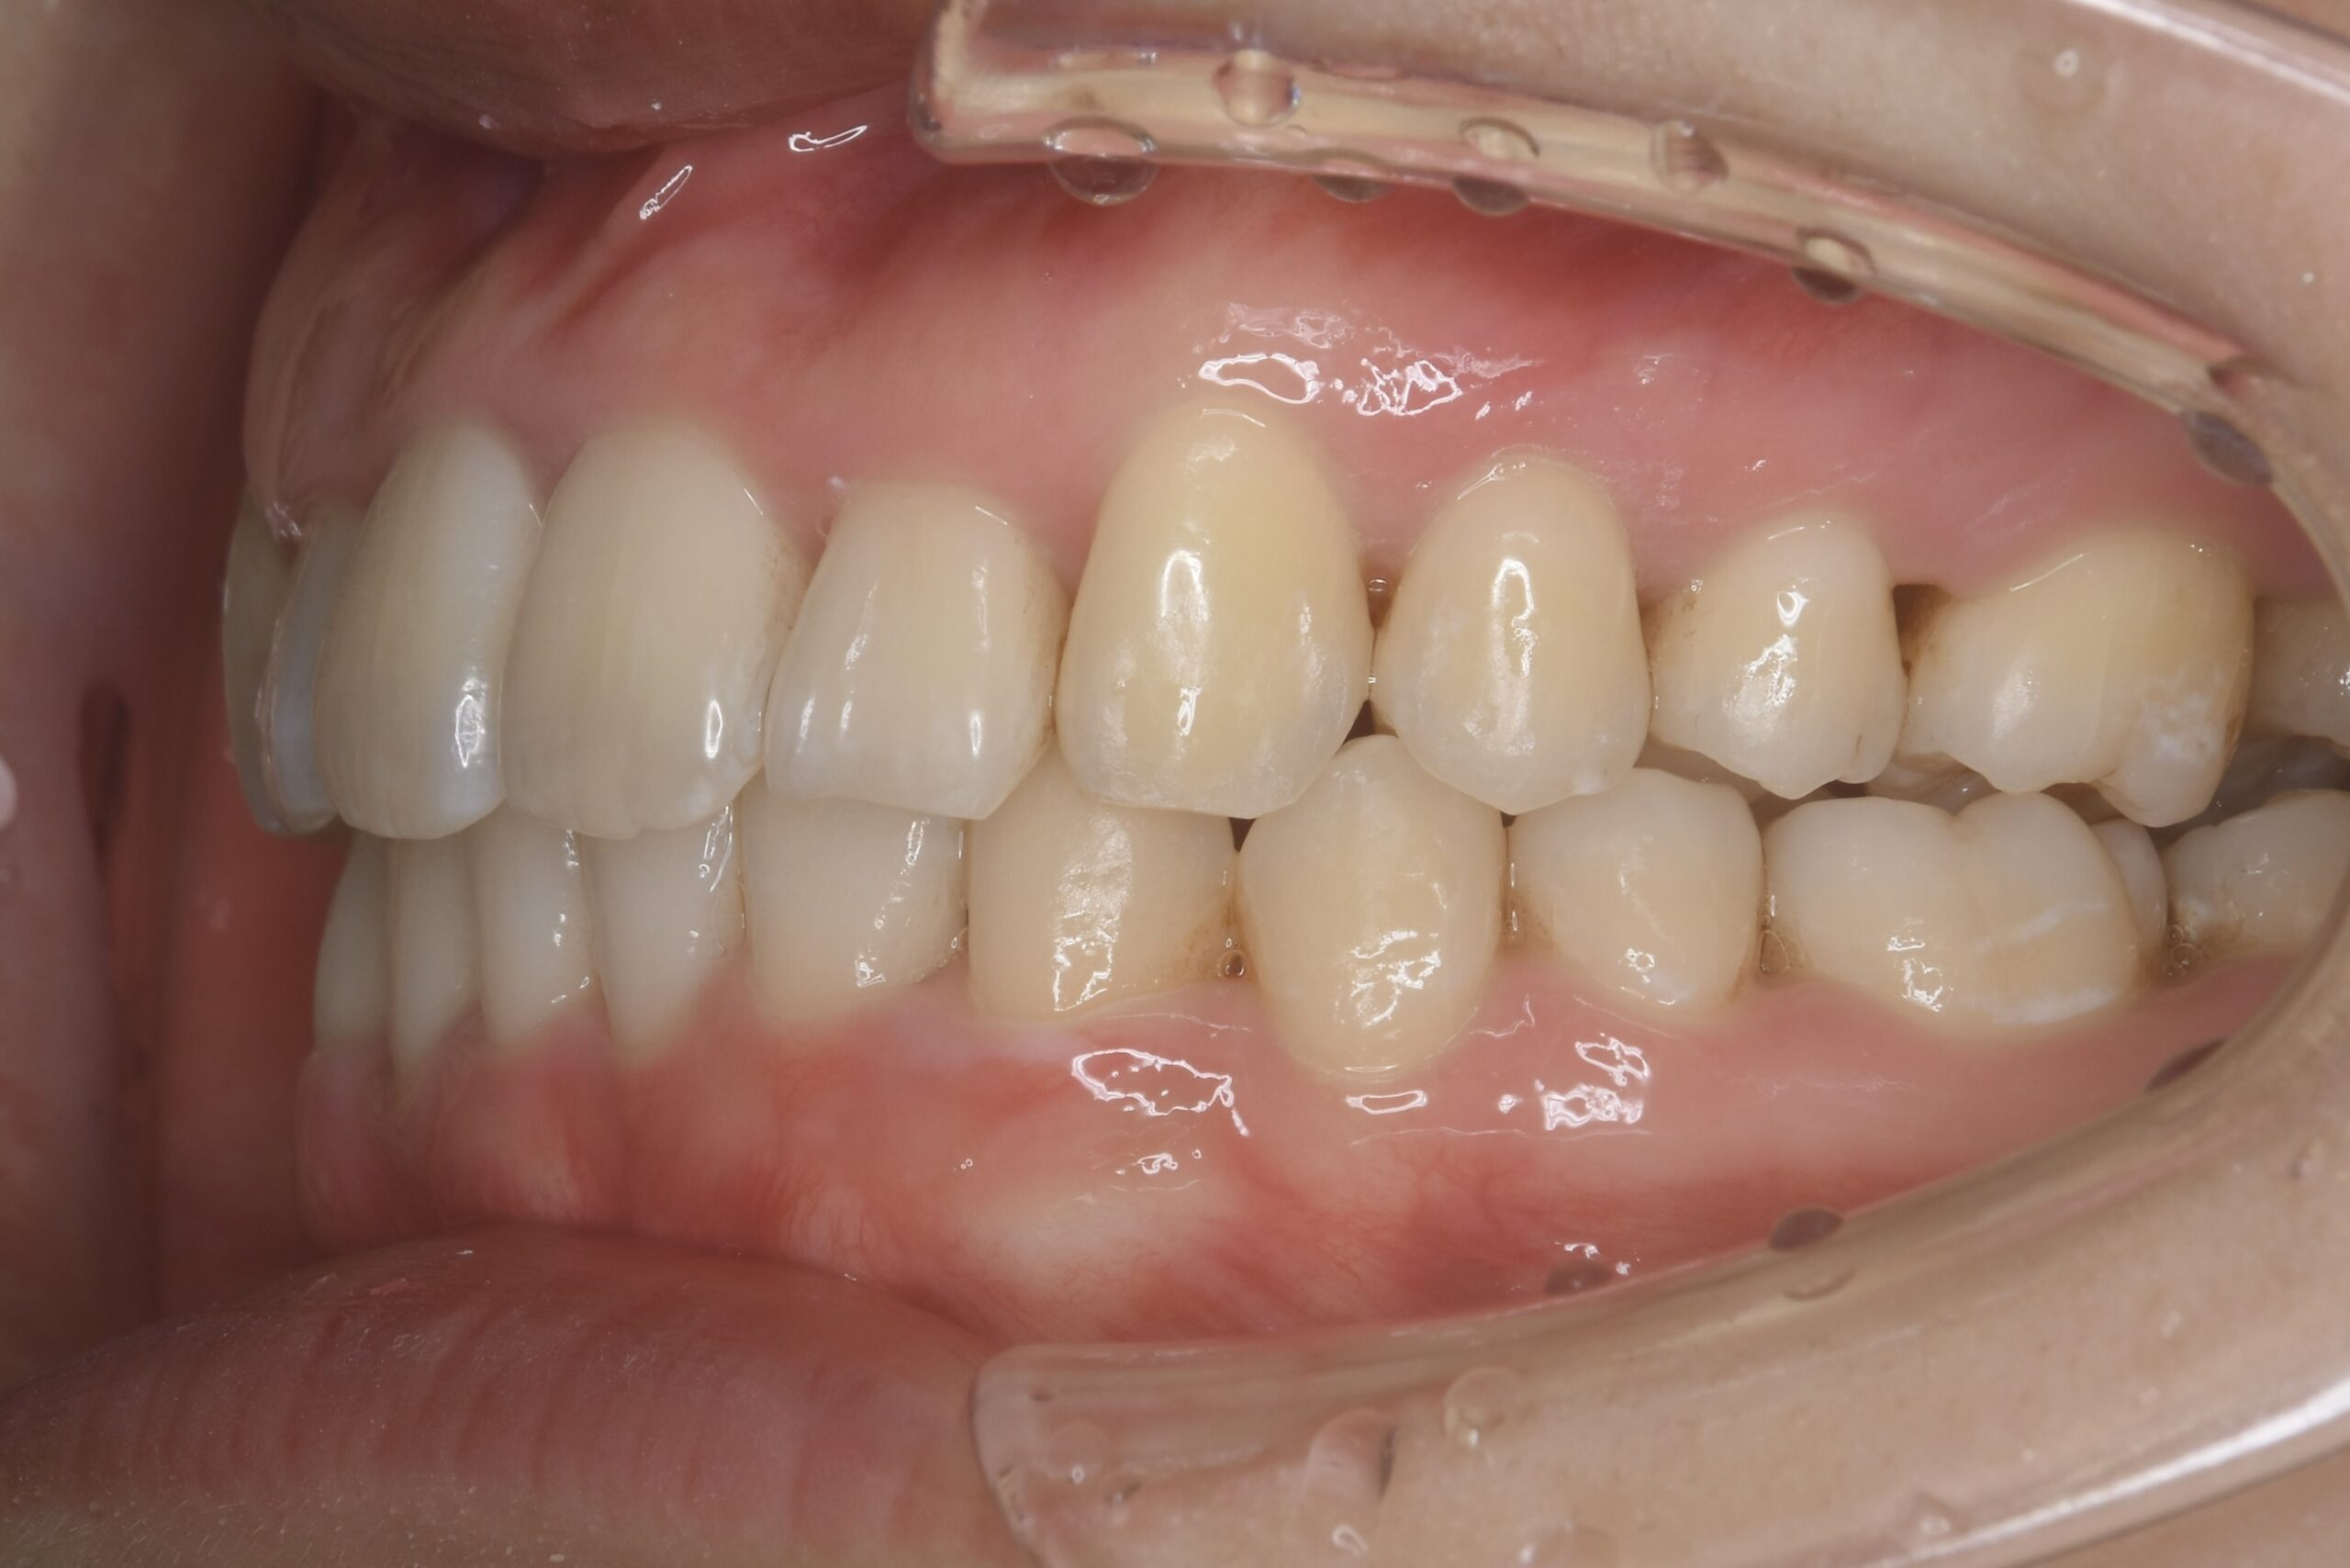

AFTER

上下とも歯並びの横幅を広げながら、でこぼこを解消しました。

マウスピース矯正(インビザライン)

抜歯あり(智歯抜歯)

治療期間

リスク・副作用

痛み、歯肉退縮、歯根吸収、抜歯に伴う出血や腫れが生じることがあります。